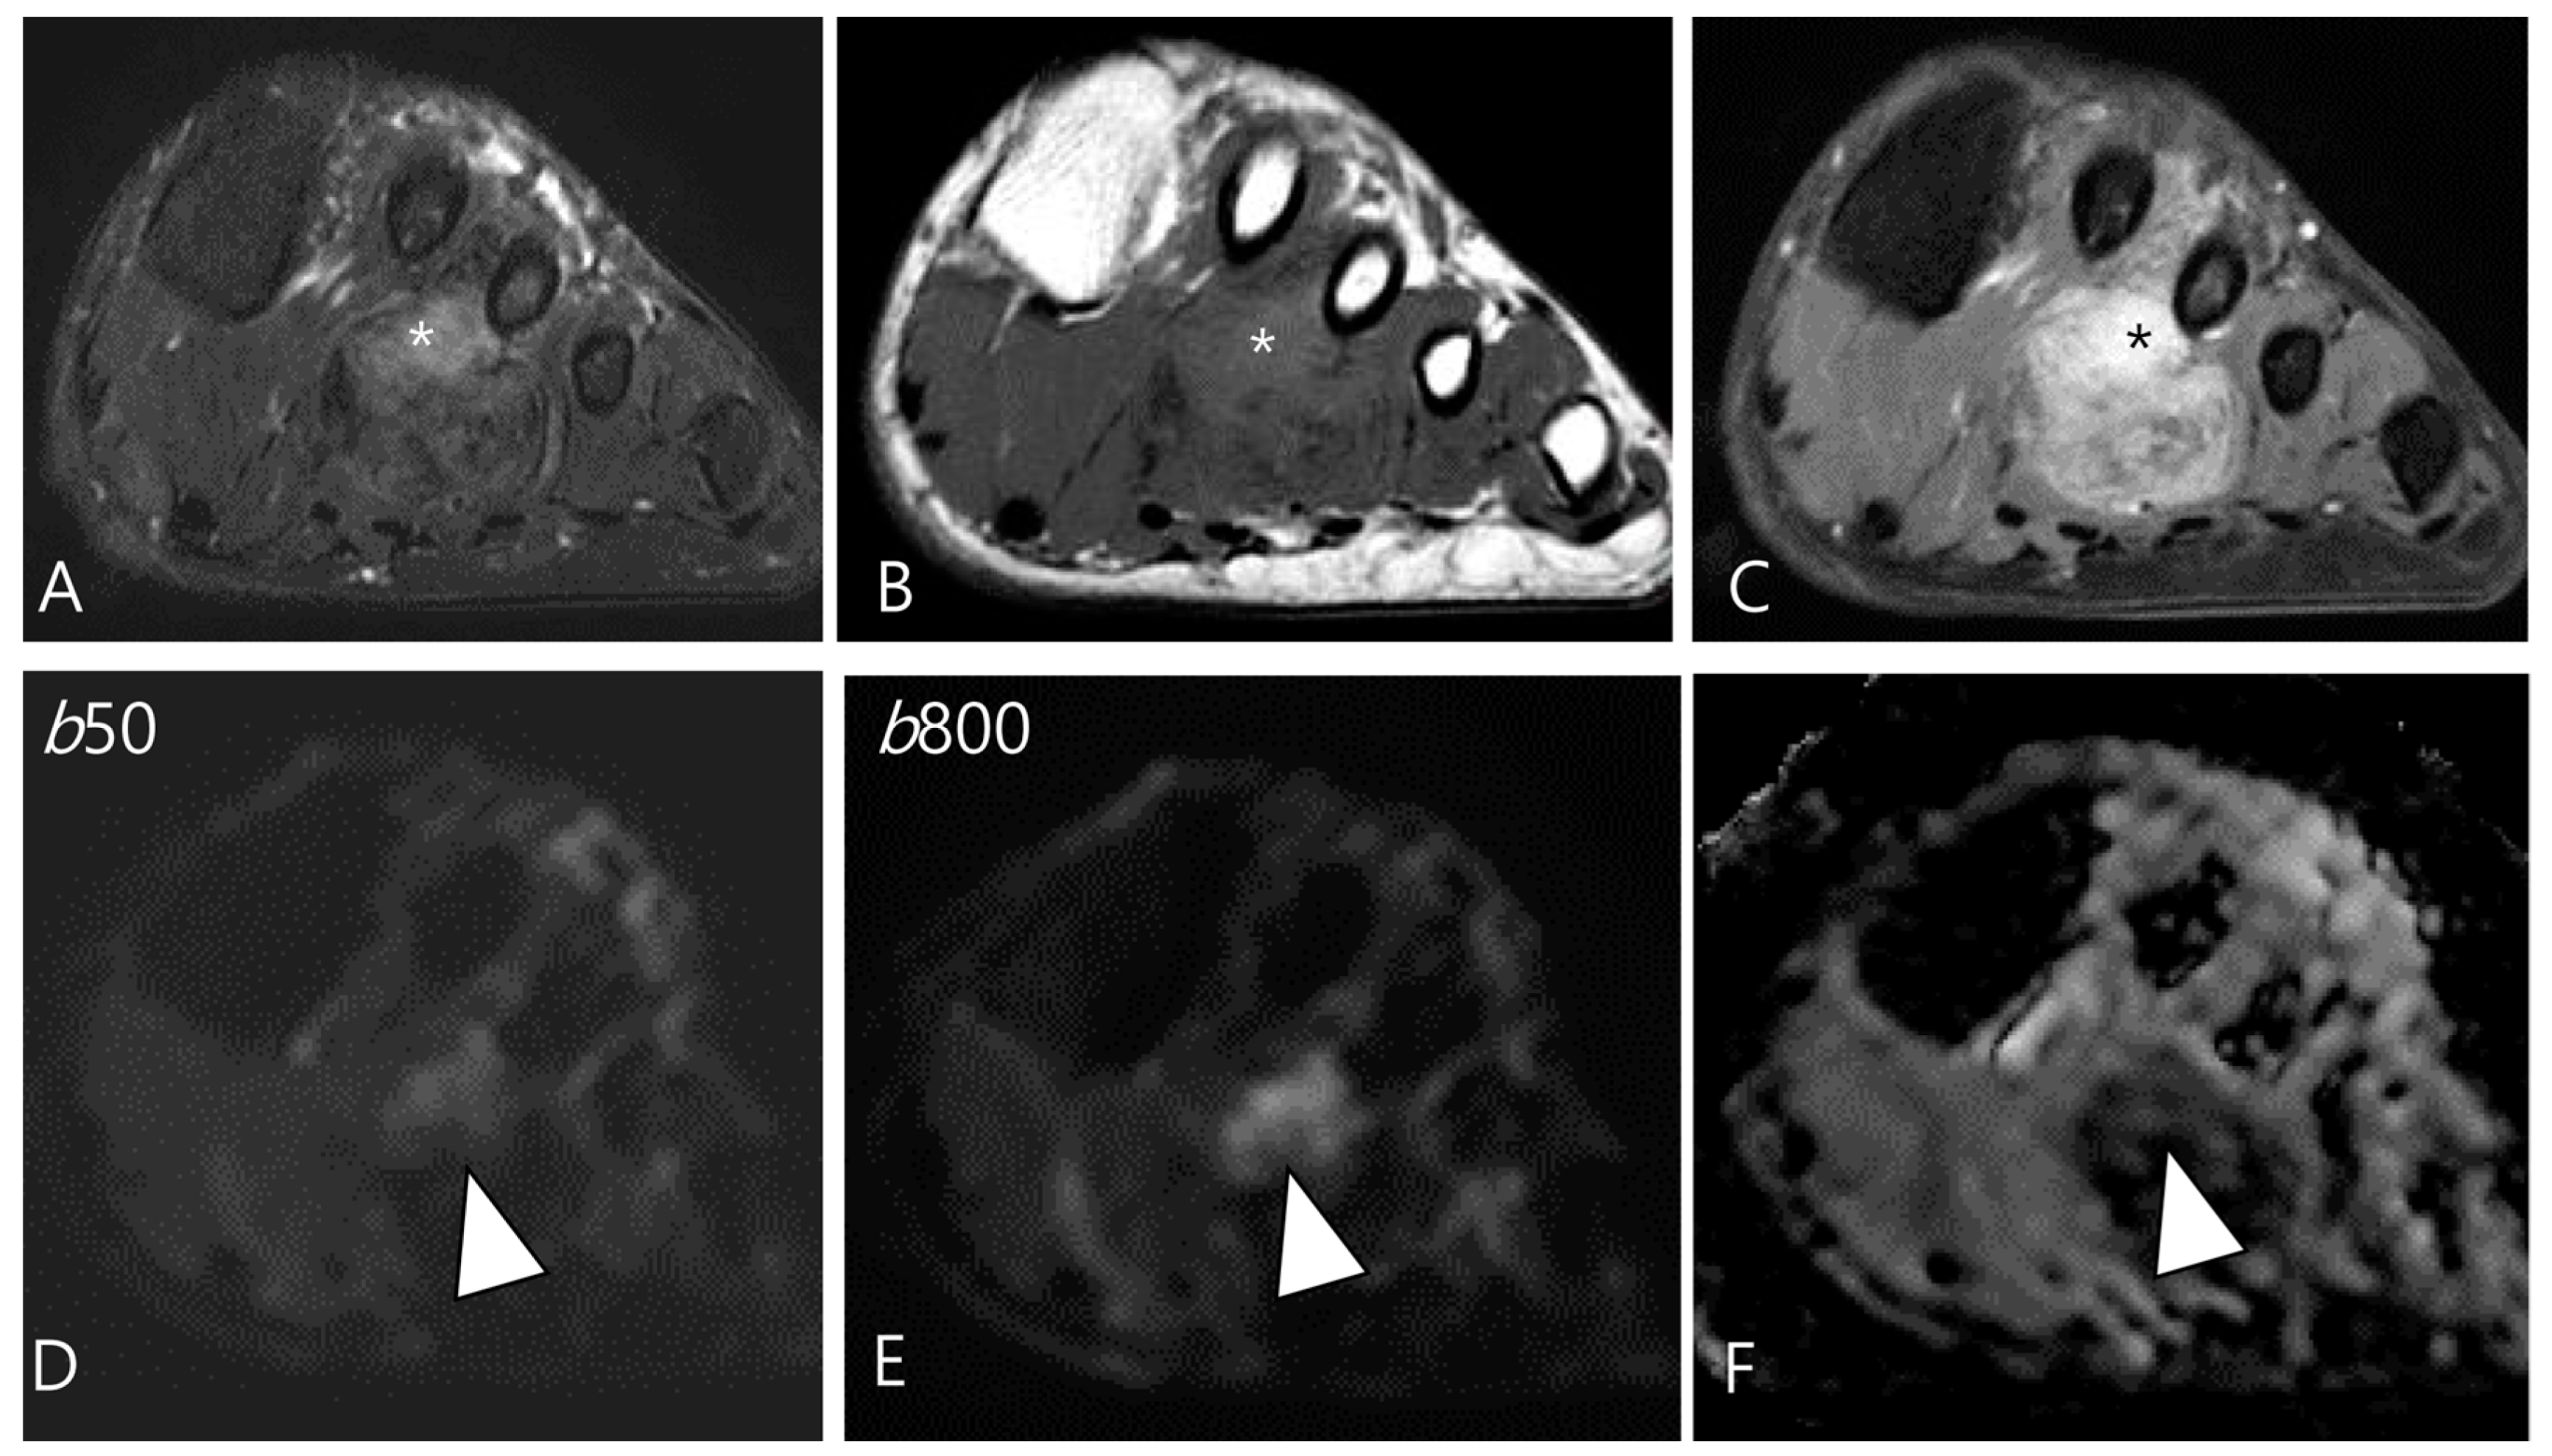

3.2.1. Fibroma of the Tendon Sheath (FTS)

- Ge, Y.; Guo, G.; You, Y.; Li, Y.; Xuan, Y.; Jin, Z.W.; Yan, G. Magnetic resonance imaging features of fibromas and giant cell tumors of the tendon sheath: Differential diagnosis. Eur. Radiol. 2019, 29, 3441–3449. [Google Scholar] [CrossRef]

- De Beuckeleer, L.; De Schepper, A.; De Belder, F.; Van Goethem, J.; Marques, M.C.; Broeckx, J.; Verstraete, K.; Vermaut, F. Magnetic resonance imaging of localized giant cell tumour of the tendon sheath (MRI of localized GCTTS). Eur. Radiol. 1997, 7, 198–201. [Google Scholar] [CrossRef]

- Hitora, T.; Yamamoto, T.; Akisue, T.; Marui, T.; Nagira, K.; Ohta, R.; Kurosaka, M. Fibroma of tendon sheath originating from the knee joint capsule. Clin. Imaging 2002, 26, 280–283. [Google Scholar] [CrossRef] [PubMed]